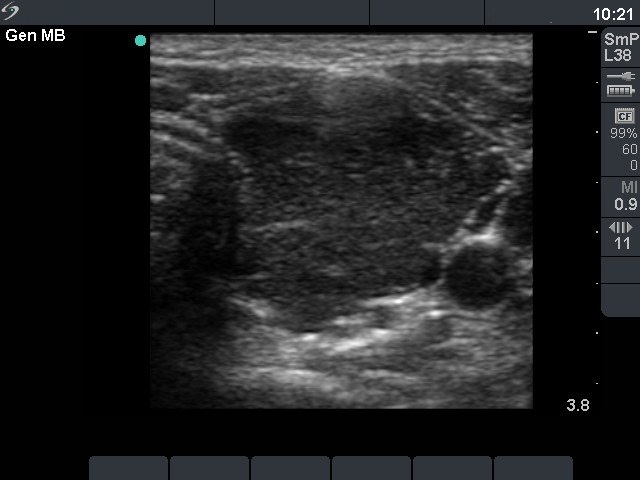

Second examination 3 months later (3rd row of images)

Clinical presentation: the complaints of the patient had decreased.

Palpation: no abnormality.

Functional state: euthyroidism with TSH-level 3.60 mIU/L, FT4 13.1 pM/L.

Ultrasonography: the degree of hypoechogenicity and the previously increased vascularization have decreased, as did the size of the thyroid.

We suggested follow-up examination with yearly TSH determination, in the case of pregnancy at once.